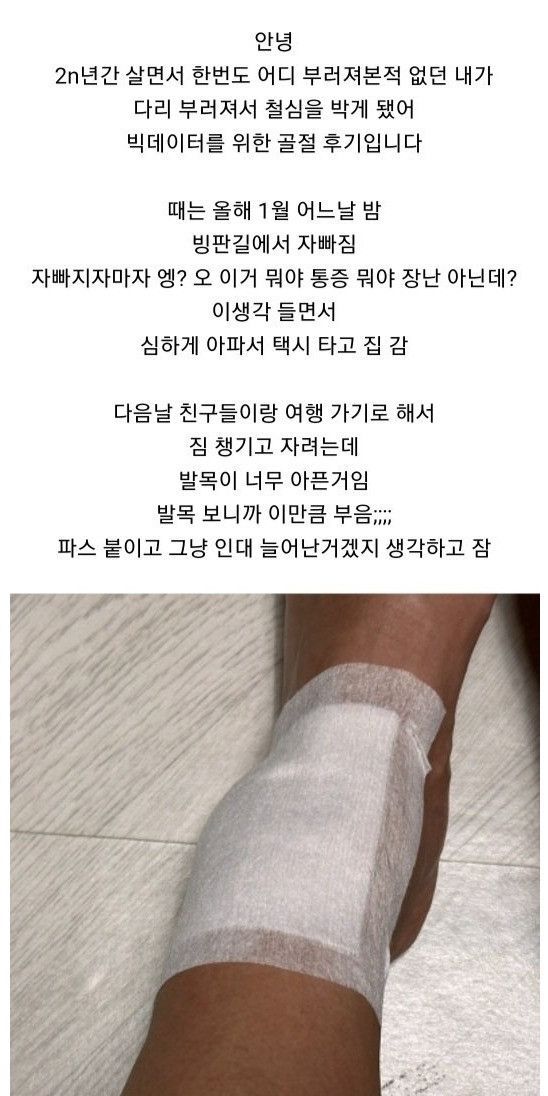

빙판길에서 자빠져 발목 부러져서 수술